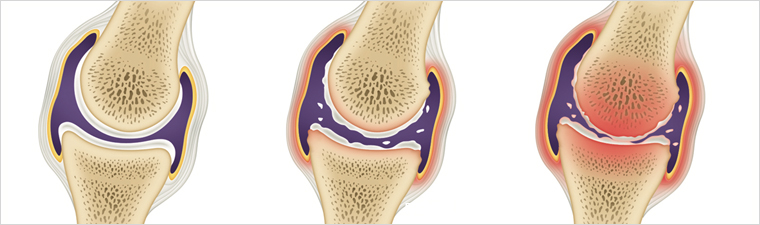

관절염의 원인은 단일하지 않으며, 병원체 감염, 유전적 취약성, 환경적 요인 등이 복합적으로 작용합니다. 원인을 알 수 없는 자가면역성 염증이 관절을 공격하면서 양쪽성 활막염을 일으키고, 장기적으로는 관절 파괴와 기능 저하를 초래할 수 있습니다.

대부분 환자는 시간 경과에 따라 증상이 완화와 악화를 반복하며, 적절히 관리하지 않으면 관절 구조와 주변 조직이 손상되어 관절 기능 상실로 이어질 수 있습니다. 활동적인 시기인 30대 전후에도 발병할 수 있고, 고령층(60세 이상)에서도 흔히 나타납니다. 스트레스가 많은 사람이나 체중이 높은 경우 위험이 커질 수 있으며, 여성의 발병률이 남성보다 높습니다.

5. 관절 붓기

평소보다 손발이 붓거나 신발이 갑자기 꽉 끼는 느낌이 든다면 관절 내 염증과 관절액 증가를 의심해 볼 수 있습니다. 활막 부종과 관절 삼출이 반복되면 연골과 주변 조직이 손상되어 관절 변형이나 운동 제한이 생길 수 있으므로 초기에 꾸준한 치료가 중요합니다.